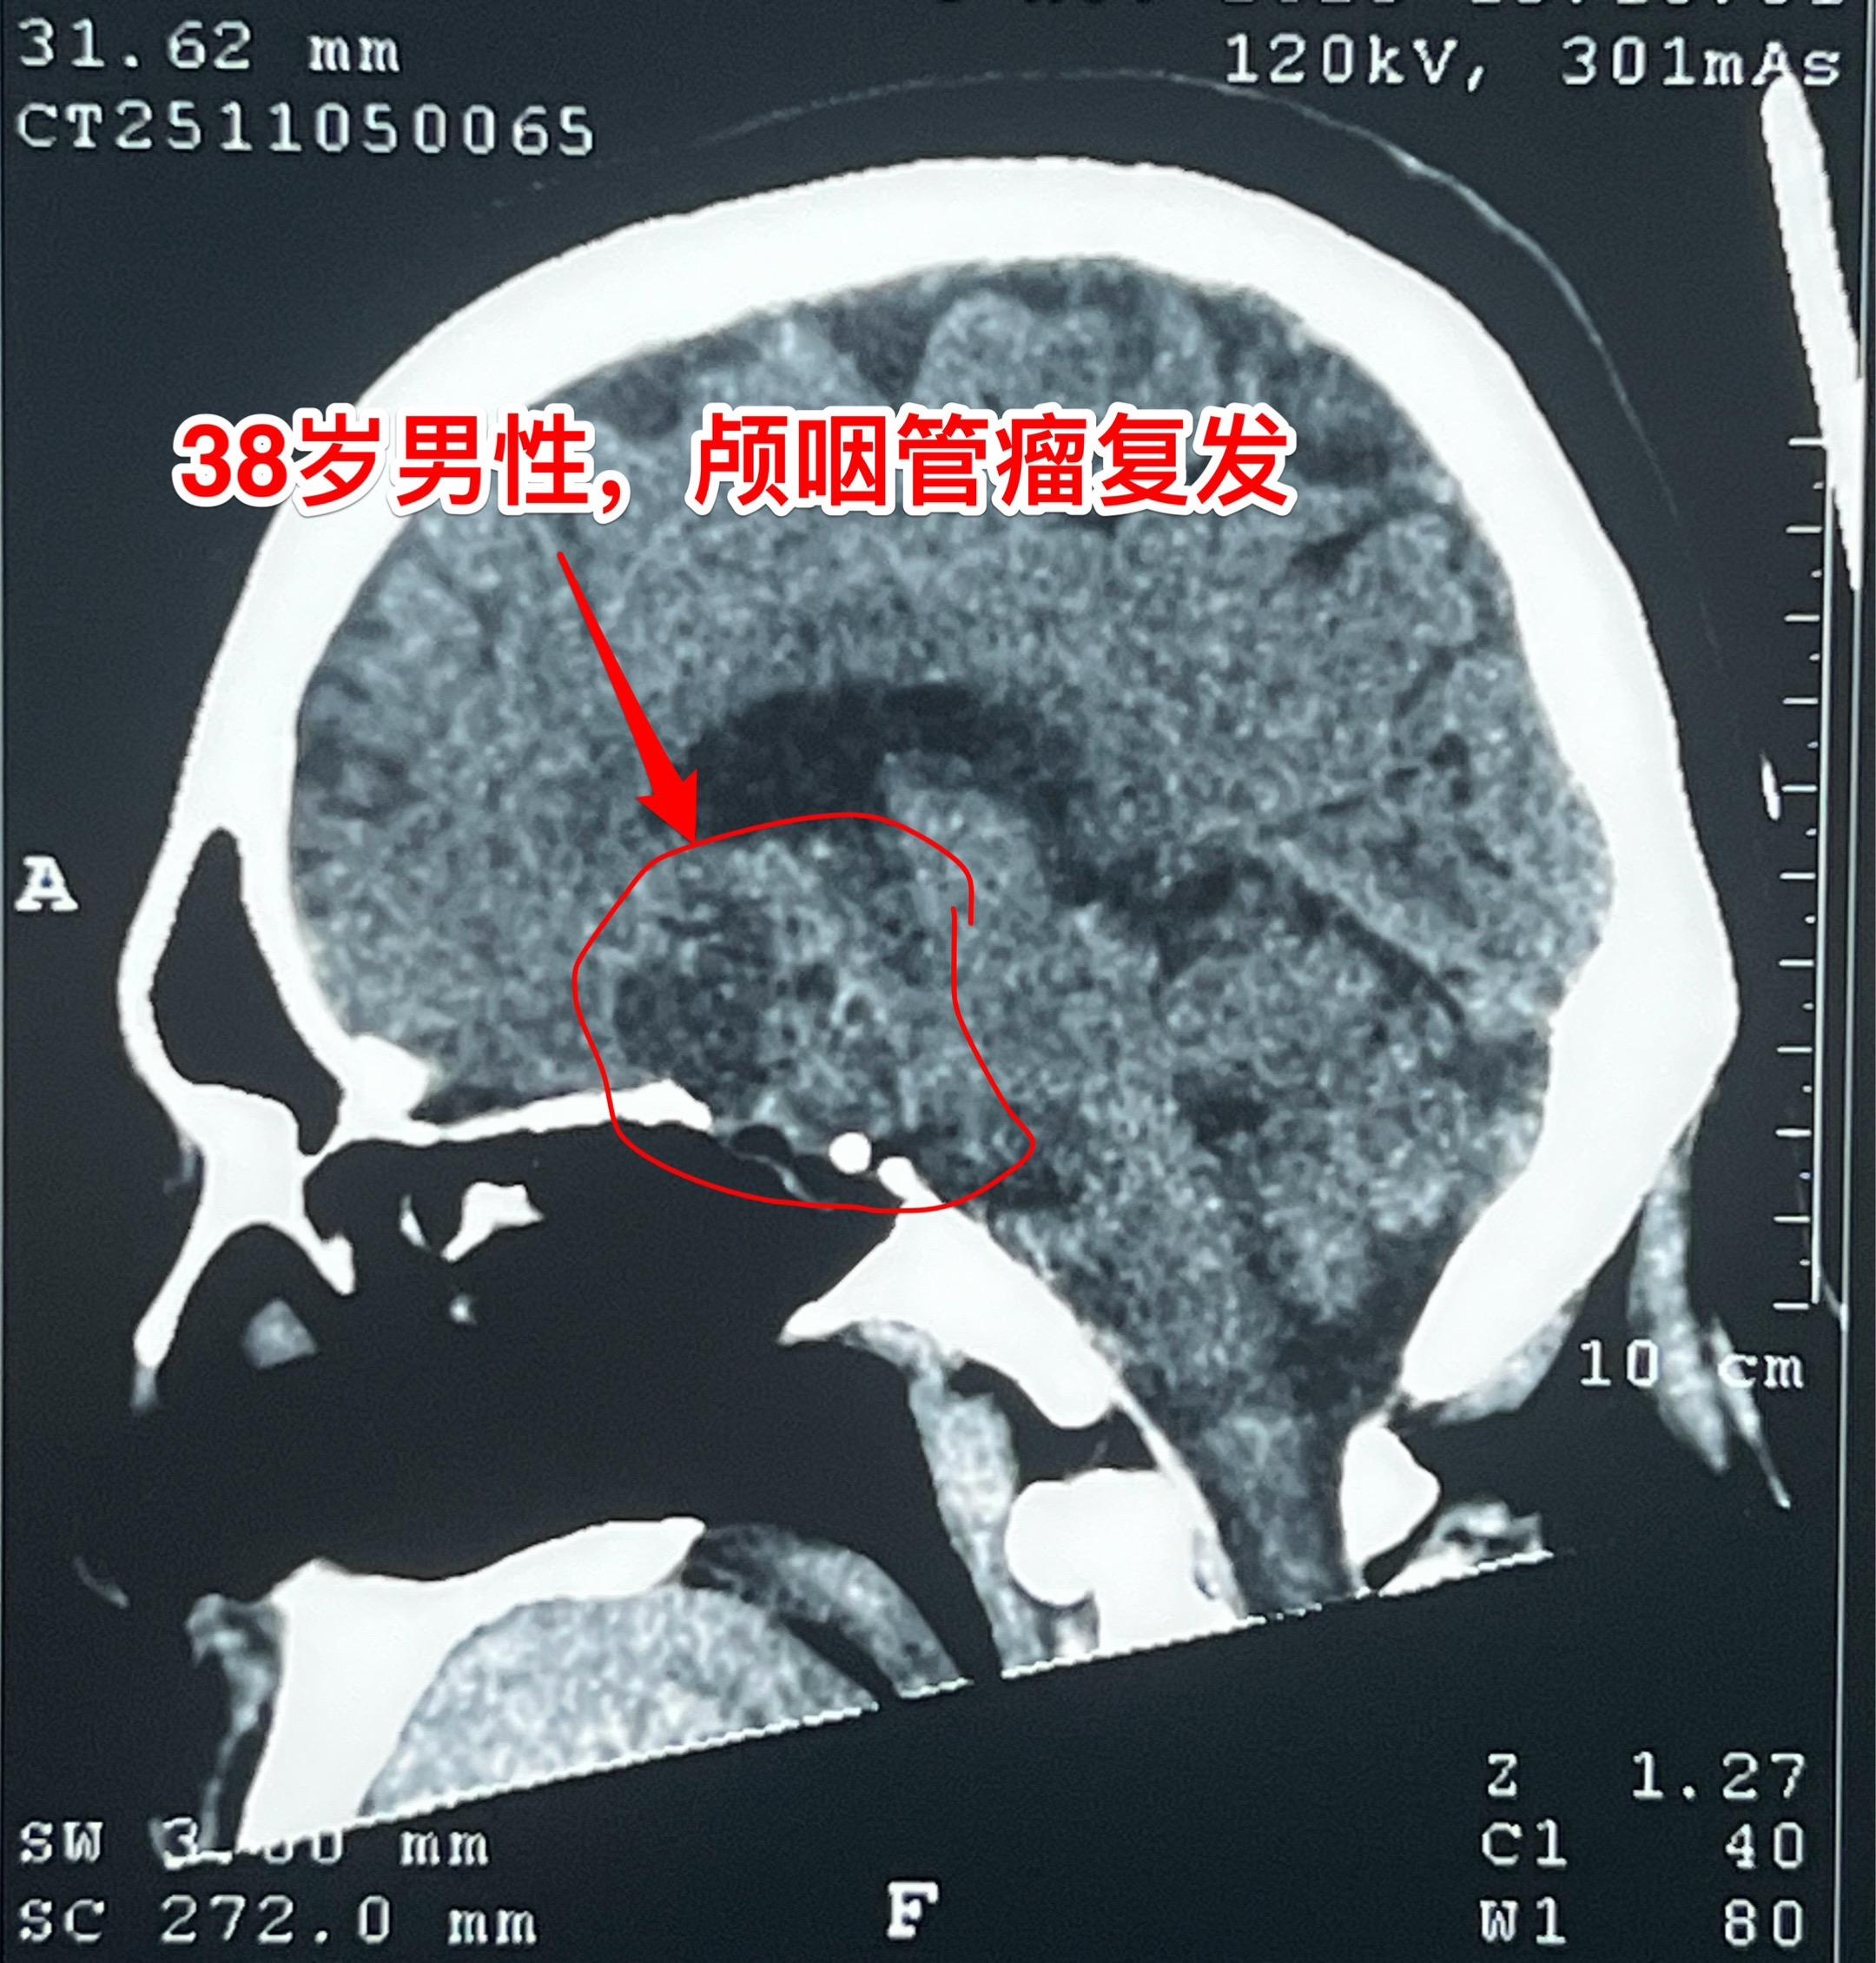

多次治疗后又复发的颅咽管瘤-不要轻易放弃。38岁福建男性,颅咽管瘤复发。 十年前因颅咽管瘤导致右眼几乎失明、右侧肢体无力,在上海行开颅手术切除颅咽管瘤,术后右眼完全失明。随后放疗一个月。2023年因颅咽管瘤复发在福建省某医院行经鼻内镜手术切除复发颅咽管瘤,肿瘤有残留。2025年5月仅有视力的左眼出现又视力下降,磁共振显示颅咽管瘤复发了,体积在增大。 病人患病十年,仍是未婚状态,家人的照顾是非常周到的。两个姐姐、两个妹妹和父母都在极力照顾他,这次得知肿瘤复发了,找到我,还是希